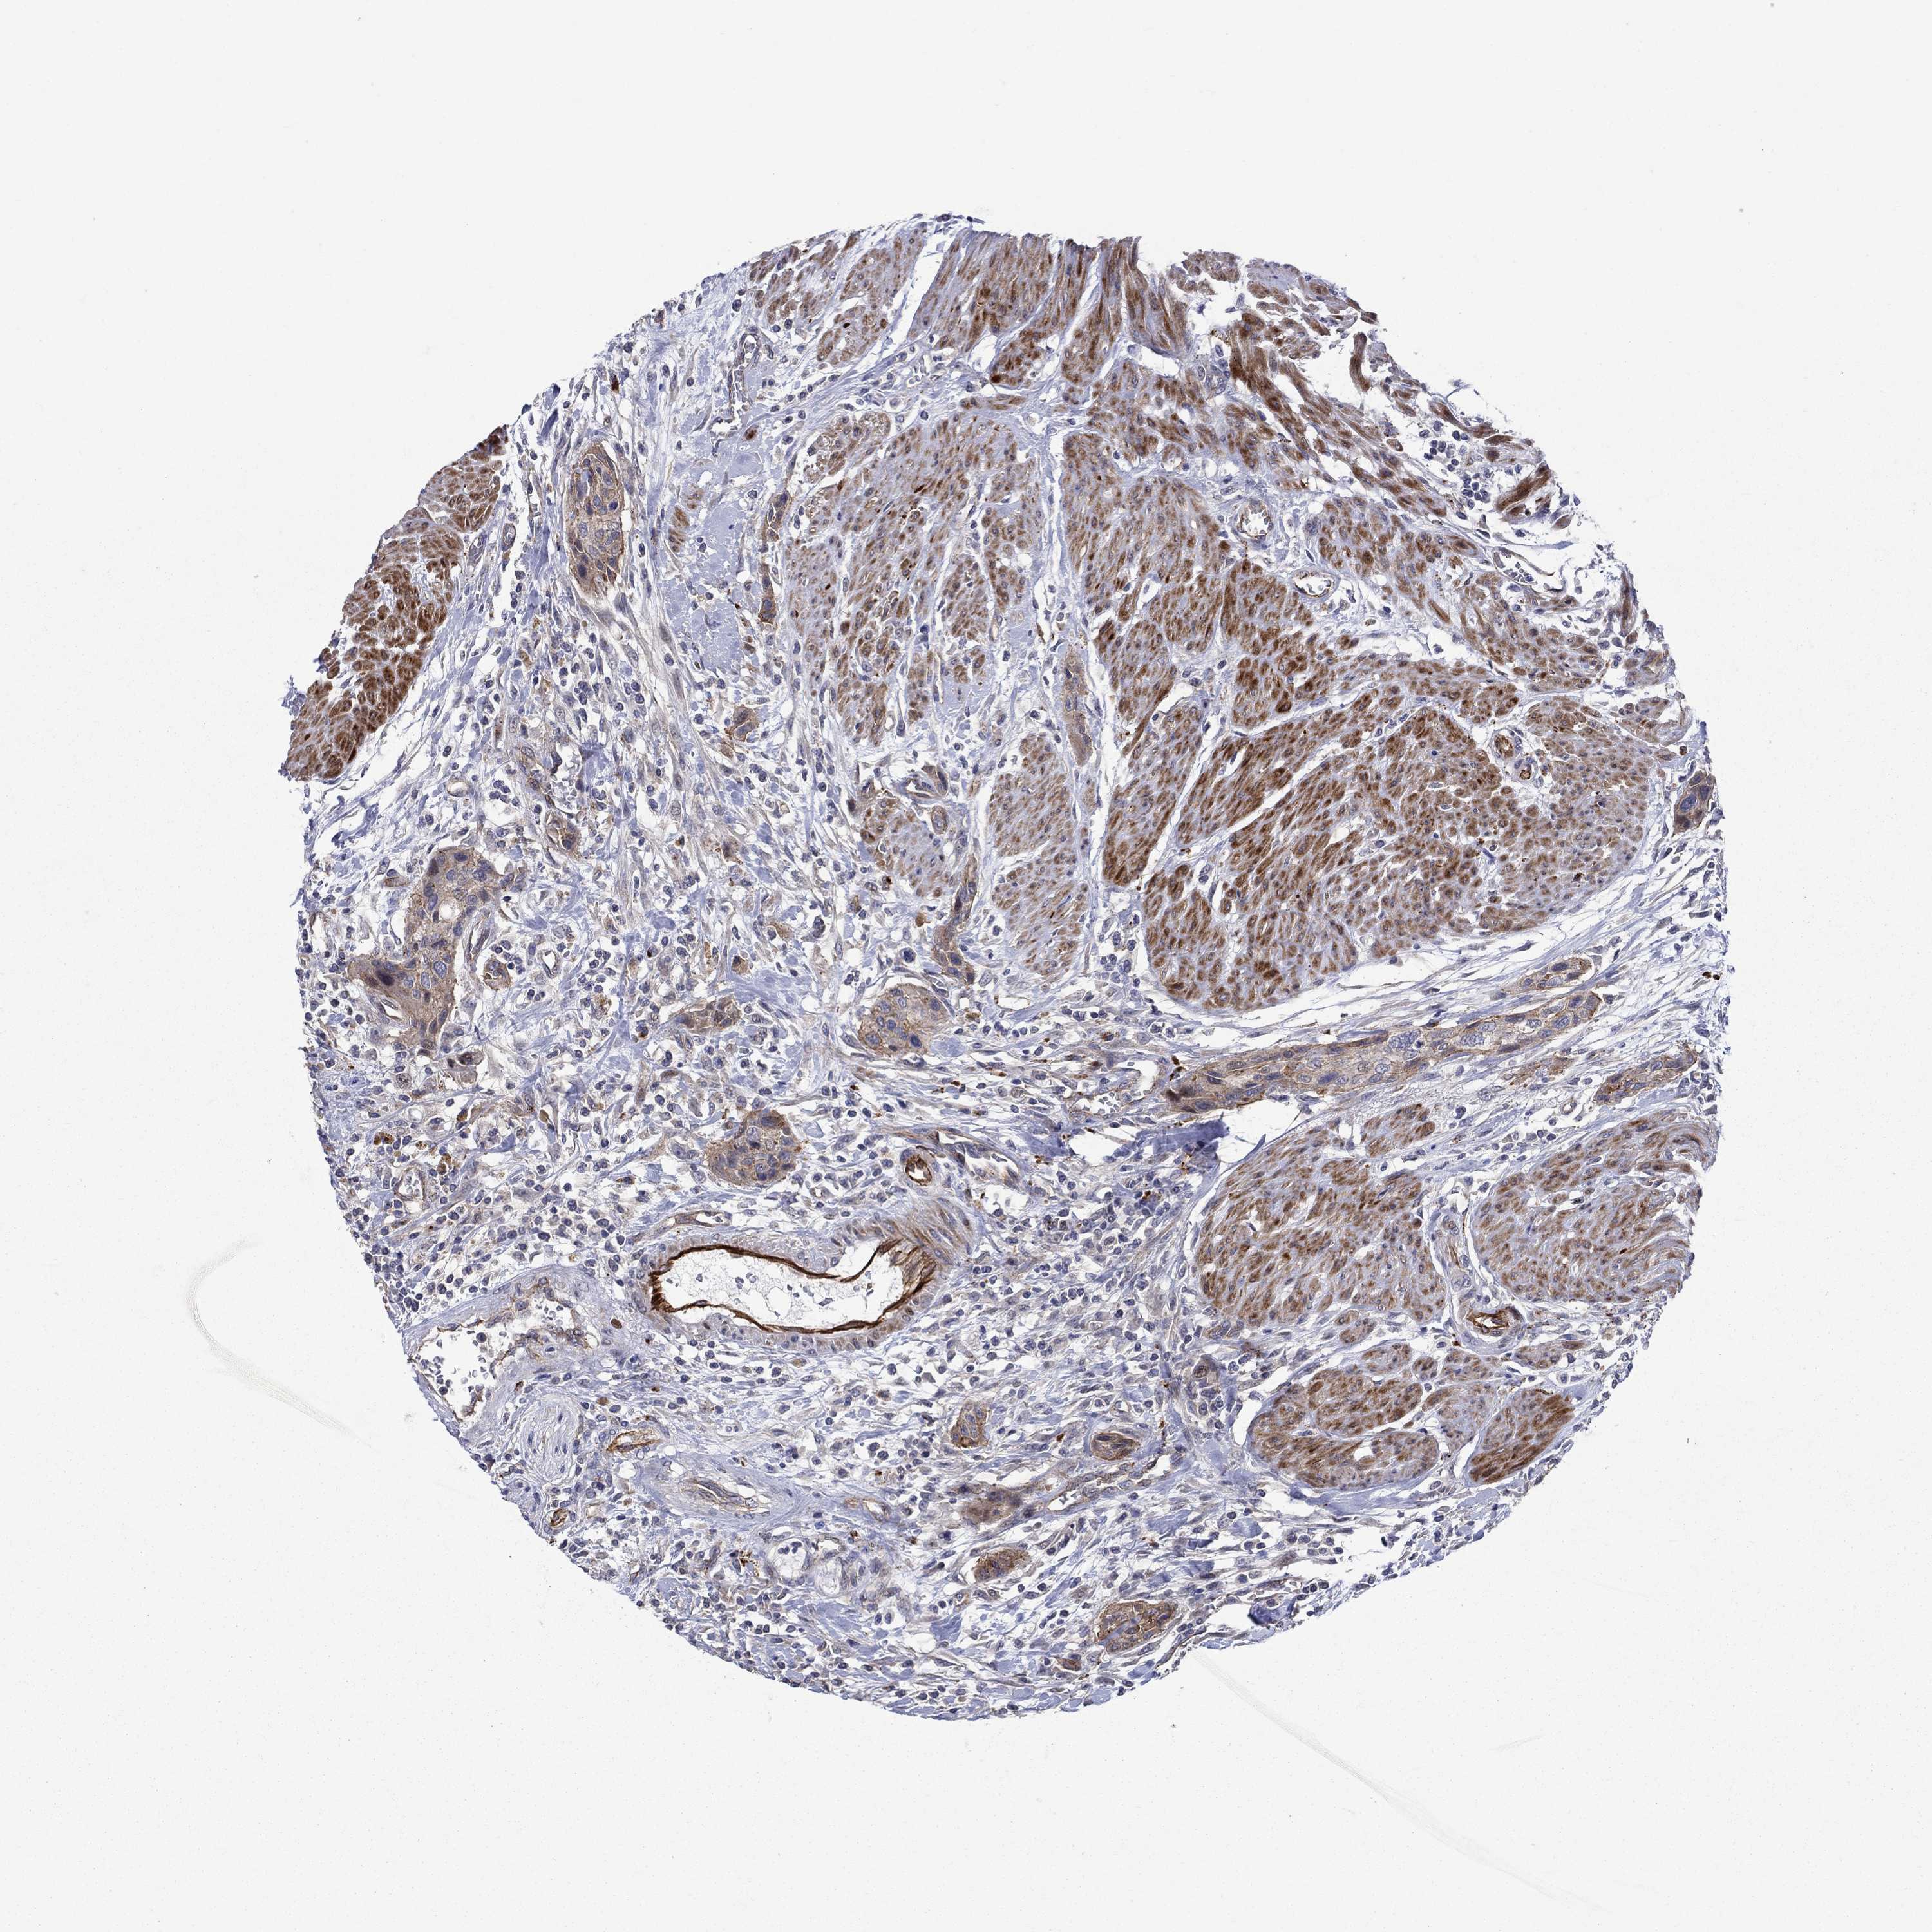

UROTHELIAL CANCER - Protein expressioni

A mouse-over function shows sample information and annotation data. Click on an image to view it in a full screen mode. Samples can be filtered based on level of antibody staining by selecting one or several of the following categories: high, medium, low and not detected. The assay and annotation is described here.

Note that samples used for immunohistochemistry by the Human Protein Atlas do not correspond to samples in the TCGA dataset.

Antibody stainingi

Antibody staining in the annotated cell types in the current human tissue is reported as not detected, low, medium, or high, based on conventional immunohistochemistry profiling in selected tissues. This score is based on the combination of the staining intensity and fraction of stained cells.

Each image is clickable and will lead to virtual microscopy that enables deeper exploration of all samples and also displays staining intensity scores, fraction scores and subcellular localization as well as patient and tissue information for each sample.

Antibody HPA039721

Antibody HPA077838

Urothelial carcinoma, High grade